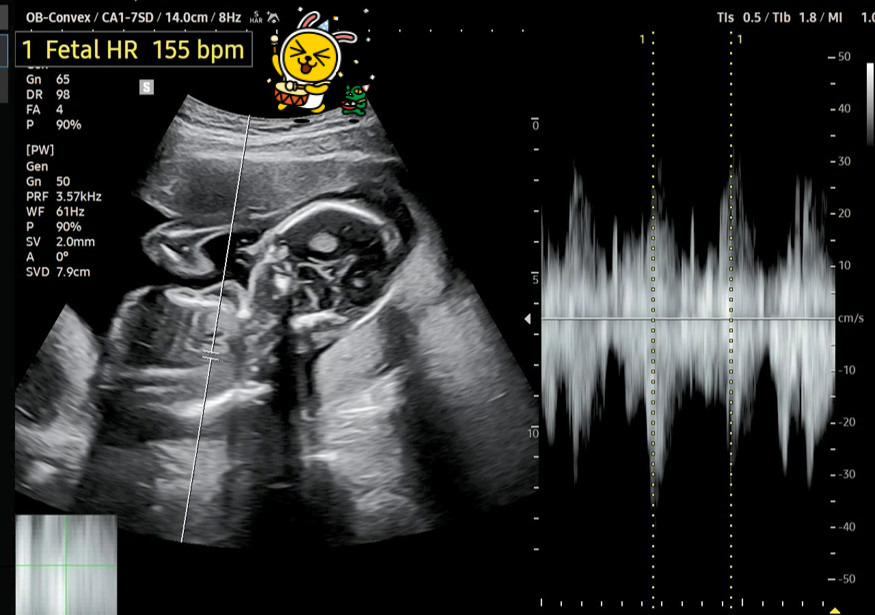

이번에 새롭게 딸애가 보내준 초음파 사진을 다시 확인해 보았습니다.

태아의 심장박동수는 155 bpm이고, 태아 머리부터 엉덩이까지의 길이(CRL)는 12.16㎝라고 나오네요.